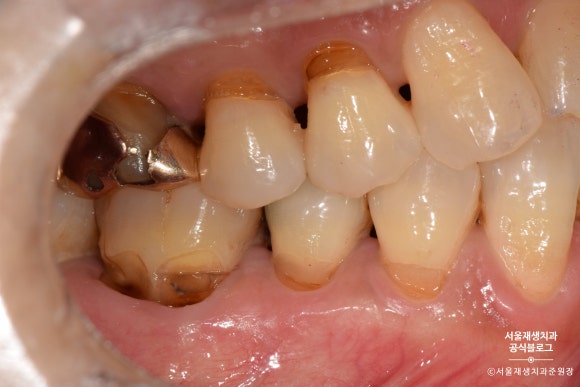

도끼로 나무를 찍어낸 듯이 좁고 깊은 케이스도 있습니다.

전방치아는 레진으로, 후방치아는 GI로 치료한 사례

여러 치아에 동시에 발생한 치경부마모증을 치료한 사례입니다.

환자분과 거울을 보며 상의한 결과,

잘 보이는 전방 치아는 레진으로,

잘 보이지 않는 후방 치아는 글라스아이오노머로 치료하기로 결정했습니다.

치아의 목 부분, 다시 말해 잇몸과의 경계 부위에

짙은 오렌지색의 띠가 보이시나요?

치아의 겉면은 하얗고 투명한 법랑질인데 반해,

치아의 속살은 노랗고 불투명한 상아질입니다.

법랑질이 모두 마모되어 상아질이 노출되었고,

법랑질에 비해 무른 상아질이 안으로 파고들듯이 마모되고 있는 상태였습니다.

제법 진행이 많이 된 치아를 선별하여

총 4개의 치아를 치료하기로 했습니다.

노란색으로 표시된 치아들은 상대적으로 전방에 위치하여 레진으로 치료하기로 했습니다.

연두색으로 표시된 치아들은 상대적으로 후방에 위치하여, 심미성이 조금 떨어지더라도 비용이 저렴한 글라스아이오노머로 치료하기로 했습니다.